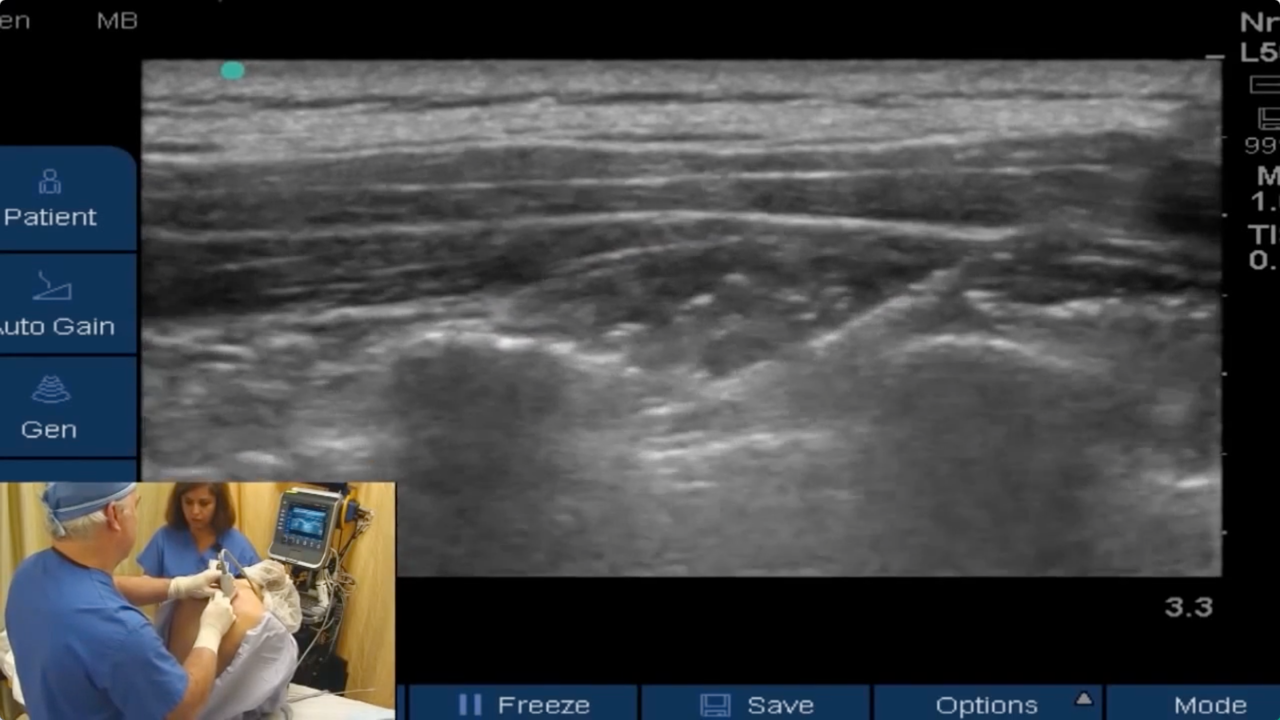

• Part 2 of 3: Can a Saphenous/Adductor Canal Block Replace a Femoral for ACL? Saphenous/Adductor Canal Block

Brandon Winchester performs a dry femoral catheter (part 1), saphenous/adductor canal block (part 2), and popliteal block (part 3) for ACL surgery in an ongoing effort to assess the saphenous block as a suitable replacement for a femoral block.